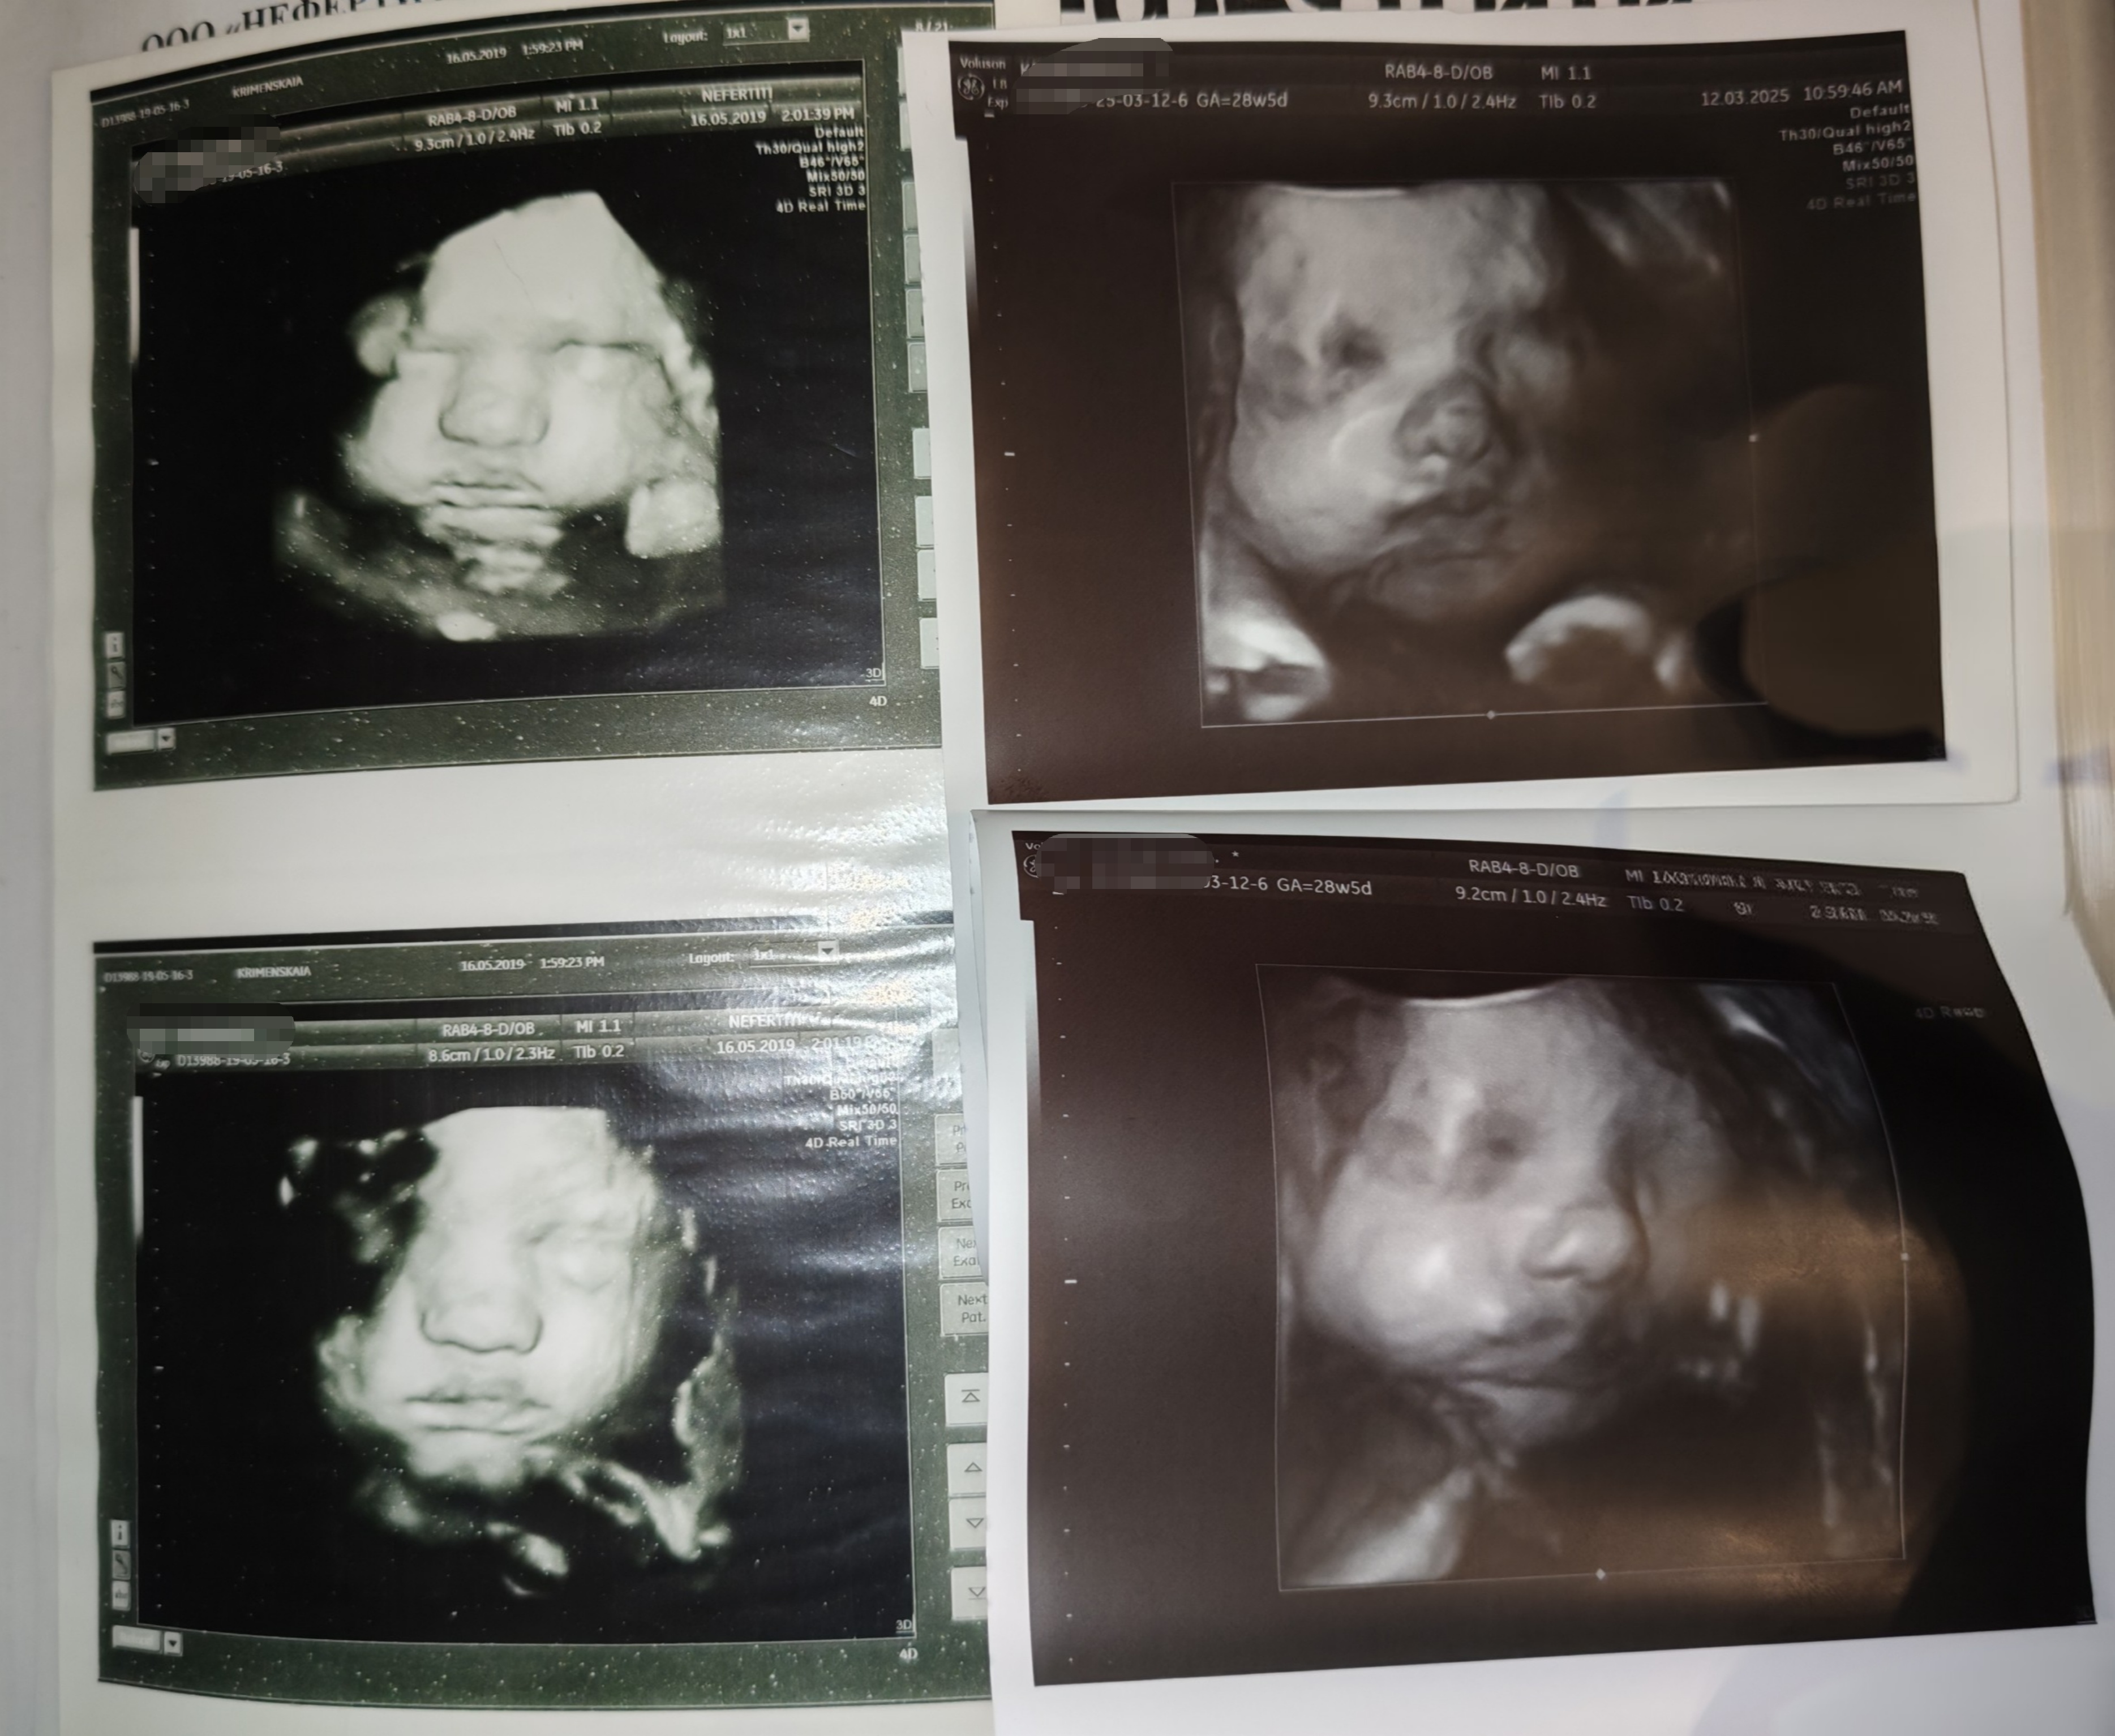

Радиомама, щёки да, хомяк такой 😅 сравнила с первой дочкой, даже что-то общее есть 😆 (первая доча слева, срок примерно одинаковый) ой, я узи обожаю делать 😆 хлебом не корми, дай на узи сбегать) я у этого врача и с первой дочкой узи делала и со второй, но вот с января к ней вообще что-то попасть невозможно было 😑 пришлось несколько узи делать в других местах, не то пальто, конечно. А тут она и меня знает и все рассказывает, показывает, разрешает на телефон видео снимать, а когда 3д включила, у меня вообще сегодня поросячий восторг был 😆 Изображение

Радиомама, Первая да, родилась 3260гр) да и эта, думаю, примерно такая же будет, там ещё мне кажется в воде всё раскисает у них 😆😆😆